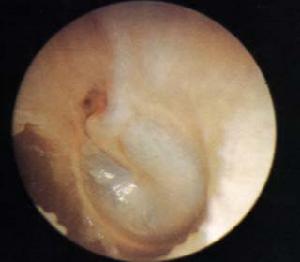

鼓膜破裂後,可突感耳痛、聽力減退、耳鳴,少量出血和耳內悶塞感。爆震傷除引起鼓膜破裂外,還可由於鐙骨強烈運動而致內耳受損,出現眩暈、噁心或混合性聾。檢查可見鼓膜多呈裂隙狀穿孔,穿孔邊緣有少量血跡,外耳道有時可見血跡或血痂。若有水樣液流出,示有顱底骨折所致腦脊液耳漏。耳聾屬傳導性或混合性。

(4) 外傷性鼓膜破裂的形態依其致傷方式的不同各有其特點;掌擊或爆震所致鼓膜穿孔形狀不一,可為梭形、裂隙形或不規則形,可見其邊緣不整齊或內翻。本組梭形及不規則形穿孔較多,邊緣內翻;器械傷所致穿孔形狀各異,本組毛線針刺傷者為圓形,另兩例尖銳物刺傷者分別為梭形及不規則形。

值得注意的是,隨著時間的推移,外傷性鼓膜破裂的情況可發生一定程度的變化,尤其繼發感染者,可失去外傷性鼓膜穿孔的特有形態,而小的破裂可在短時間內癒合,這為我們的傷情評定增加了難度。鑒於此,我們常對外傷性鼓膜破裂者,早期錄像,以記錄傷後鼓膜破裂的初期表現,為以後鑑定提供較為客觀的依據。

鼓摸破裂時情緒緊張,可不覺任何症狀。 傷後,突覺耳內轟鳴、伴有耳痛、 耳鳴、 耳聾或突然耳聾. 有少量血從外耳道流出;如伴有內耳損傷,則有眩暈、噁心和重度耳聾。檢查時可見外耳道有血跡,鼓膜有不規則的穿孔。

鼓摸破裂時情緒緊張,可不覺任何症狀。 傷後,突覺耳內轟鳴、伴有耳痛、 耳鳴、 耳聾或突然耳聾. 有少量血從外耳道流出;如伴有內耳損傷,則有眩暈、噁心和重度耳聾。檢查時可見外耳道有血跡,鼓膜有不規則的穿孔 。